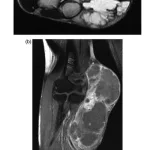

8時前に病棟に上がり, 昨日手の軟部腫瘍を摘出した患者さんの様子を確認.

術後の経過は良好で, 神経障害もなく, 創部のガーゼをシールタイプに交換して退院していただきました.